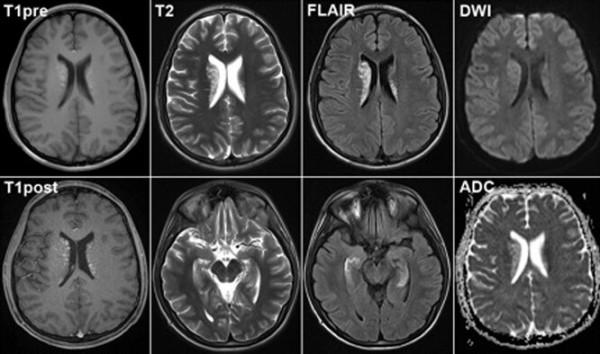

事實上,文章認為,有一個FMRI將記錄兩個對立點的同步活動,這將證明我們無法訪問的4D現實的存在,我們的大腦居住。